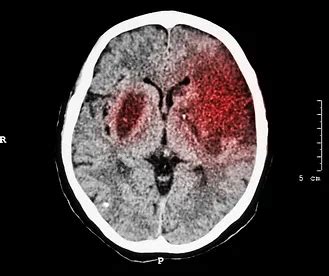

When someone rushes into the emergency department with suspected stroke symptoms , the very first imaging test they’ll likely get, hands down, is a non-contrast head CT scan . Why, you ask? Because, guys, speed is of the essence, and CT scans are fast , readily available in most hospitals, and excel at ruling out the worst-case scenario – a hemorrhagic stroke . Remember how we talked about ischemic stroke being a blockage? Well, a hemorrhagic stroke is a bleed, where a blood vessel bursts in the brain. Giving clot-busting medication (like tPA) to someone with a brain bleed would be catastrophic, making the bleeding much, much worse. So, the primary goal of that initial CT scan is to rapidly differentiate between these two types of strokes. If the CT scan shows no signs of hemorrhage , then the pathway opens up for ischemic stroke treatments. It’s like a crucial fork in the road, and the CT scan points the way.

Now, here’s a critical point about ischemic stroke CT scan images in the acute phase (meaning, right after the stroke starts): early ischemic changes can be incredibly subtle, or even non-existent , on a standard non-contrast CT scan for the first few hours. This can be super confusing for folks who expect a clear “stroke” visible right away. In the very first hour or two, the brain tissue often looks perfectly normal on CT, even though it’s dying! This phenomenon is why clinical presentation (the patient’s symptoms) is so vital alongside the imaging. However, as time passes, typically within 3 to 6 hours, more definite signs of ischemia begin to appear. The radiologist is looking for these early signs of ischemic stroke with a trained eye, even if they are faint. The absence of hemorrhage, coupled with the clinical picture, is often enough to initiate thrombolytic therapy (like tPA) within the crucial treatment window , which is typically within 4.5 hours of symptom onset for tPA, and up to 24 hours for mechanical thrombectomy in select cases. This entire process highlights the incredibly high stakes involved. The CT scan isn’t just a diagnostic tool; it’s a critical decision-making instrument that guides urgent, potentially life-saving interventions, making every detail on those ischemic stroke CT scan images profoundly important. The ability to quickly and accurately interpret these scans dictates whether a patient receives timely treatment that could literally prevent permanent disability or even save their life. So, when doctors are pouring over those images, they’re not just looking at pictures; they’re making rapid judgments about brain viability and treatment eligibility.

One of the earliest and most important CT signs of acute ischemic stroke is the dense middle cerebral artery (MCA) sign . This one is pretty cool, actually. Normally, blood vessels on a non-contrast CT aren’t super bright. But if a large clot is stuck in the MCA (which is one of the main arteries supplying blood to the brain), the clot itself, being denser than flowing blood, can appear hyperdense or brighter than the normal artery on the scan. It looks like a bright white line within the sylvian fissure or along the course of the MCA. Seeing a dense MCA sign is a strong indicator of a large vessel occlusion and usually means a significant ischemic stroke is underway. It’s an urgent red flag telling clinicians, “Hey, there’s a big blockage here, and we need to act fast!”

Another key early indicator on ischemic stroke CT scan images is sulcal effacement . What are sulci? They’re those grooves or “valleys” on the surface of your brain. When brain tissue starts to swell due to ischemia (lack of blood flow), these grooves can get pushed in and appear flattened or even disappear in the affected area. Think of it like a deflated balloon re-inflating; the wrinkles smooth out. Focal sulcal effacement signifies swelling and edema within the brain tissue, indicating that ischemic injury is progressing. It’s often seen in the insular ribbon area, which brings us to our next sign.

The insular ribbon sign , or rather, the loss of the insular ribbon sign , is another subtle but critical finding. The insula is a part of the brain located deep within the sylvian fissure, and its cortex (the outer layer) normally appears as a distinct, bright “ribbon” due to its specific density. In the early stages of an ischemic stroke , especially one affecting the MCA territory, the gray matter of the insular cortex can become edematous (swollen) and lose its normal distinct appearance. It becomes hypodense (darker) and indistinct, blending in with the surrounding white matter. This loss of gray-white differentiation is a classic early ischemic change and is often one of the first visible signs that the delicate brain tissue is being starved of oxygen.

Finally, a more generalized sign is the loss of gray-white matter differentiation . Normally, on a CT scan, you can clearly distinguish between the gray matter (where nerve cell bodies are concentrated, forming the brain’s outer cortex and deep nuclei) and the white matter (composed of nerve fibers, which appears slightly darker). In the early stages of an ischemic stroke , as brain cells swell and lose their structural integrity, this distinct boundary blur. The affected gray matter starts to look less dense, more like the white matter , making it harder to tell them apart. This blurring or effacement of the gray-white junction is a direct consequence of cytotoxic edema, where cells swell and lose water regulation, an early sign of irreversible damage. These ischemic stroke CT scan images are challenging to interpret, but recognizing these subtle cues is paramount for effective, time-sensitive stroke management. The skill required to identify these early changes really highlights the expertise of the medical professionals involved in stroke care, as every tiny hint on the scan contributes to a bigger picture that can literally save brain function.